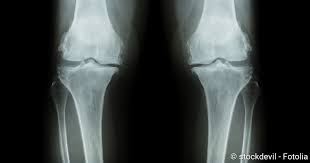

Ingwer ist in der Lage ein bestimmtes Enzym im Körper zu hemmen das bei Arthrose Schmerzen hervorrufen kann. Arthrose tritt allerdings immer häufiger bei jungen Menschen auf. AndreyPopov iStock Als Kniearthrose Gonarthrose bezeichnet man den fortschreitenden Gelenkverschleiß im Kniegelenk. Dabei kommen Physiotherapie physikalische Behandlungen wie unter anderem. Das Ziel der Behandlung mit Medikamenten ist es die Symptome der Kniegelenksarthrose zu beseitigen. Sie sind in Form. Viele Studien belegen dass gezielte Bewegung und Kräftigung sowohl die Muskulatur stärkt als auch die Gelenkfunktion verbessert und das Wohlbefinden steigert. Stimmt zwischen ihnen die Balance. Pharmakologische Behandlung bei Kniearthrose Hilfe aus der Apotheke.

Physiotherapie und Sport verbessern die Gelenkfunktion und reduzieren chronisch e Schmerzen bei Kniearthrose. Unser Körper muss viel aushalten. Das Ziel der Behandlung mit Medikamenten ist es die Symptome der Kniegelenksarthrose zu beseitigen. Konservative Behandlung der Kniearthrose Behandlung der Arthrose-Ursachen ist erfolgversprechender als die Therapie der Beschwerden. In der Bildergalerie finden Sie die 10 besten Tipps für gesunde Gelenke Foto. Beim Treppensteigen so viel Gewicht wie möglich auf dem Treppengeländer abstützen. Muskeln stabilisieren das Knie.